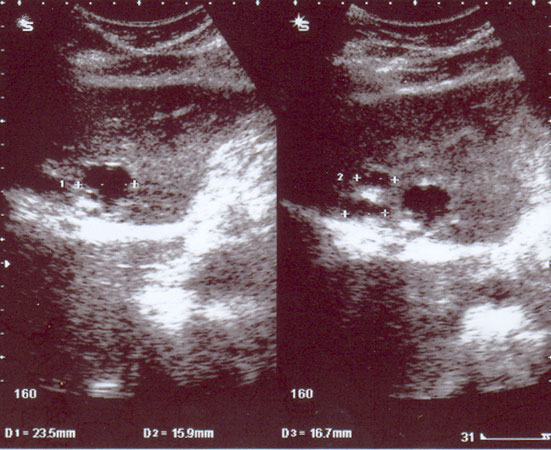

Ultrasound yang dilakukan pada tanggal 25 April 2007 menunjukkan adanya beberapa kista kecil dihatinya, tetapi tidak ada solid massa. Usus besarnya diisi dengan gas.